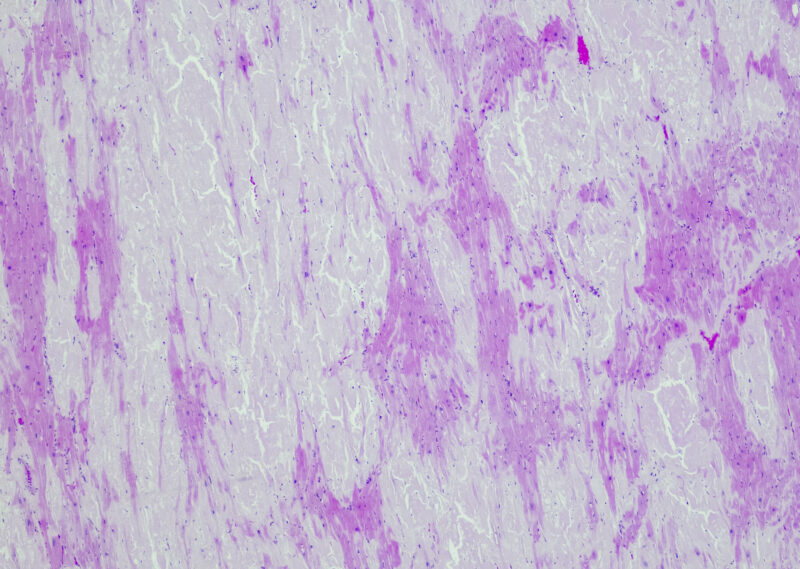

• This content is machine translated Dermatosis deposicionales

Amiloidosis: el reconocimiento precoz de los síntomas cutáneos es crucial

La amiloidosis es una forma rara de dermatosis de depósito causada por el plegamiento incorrecto de las proteínas. La detección dermatológica precoz es de gran importancia para la evolución posterior…